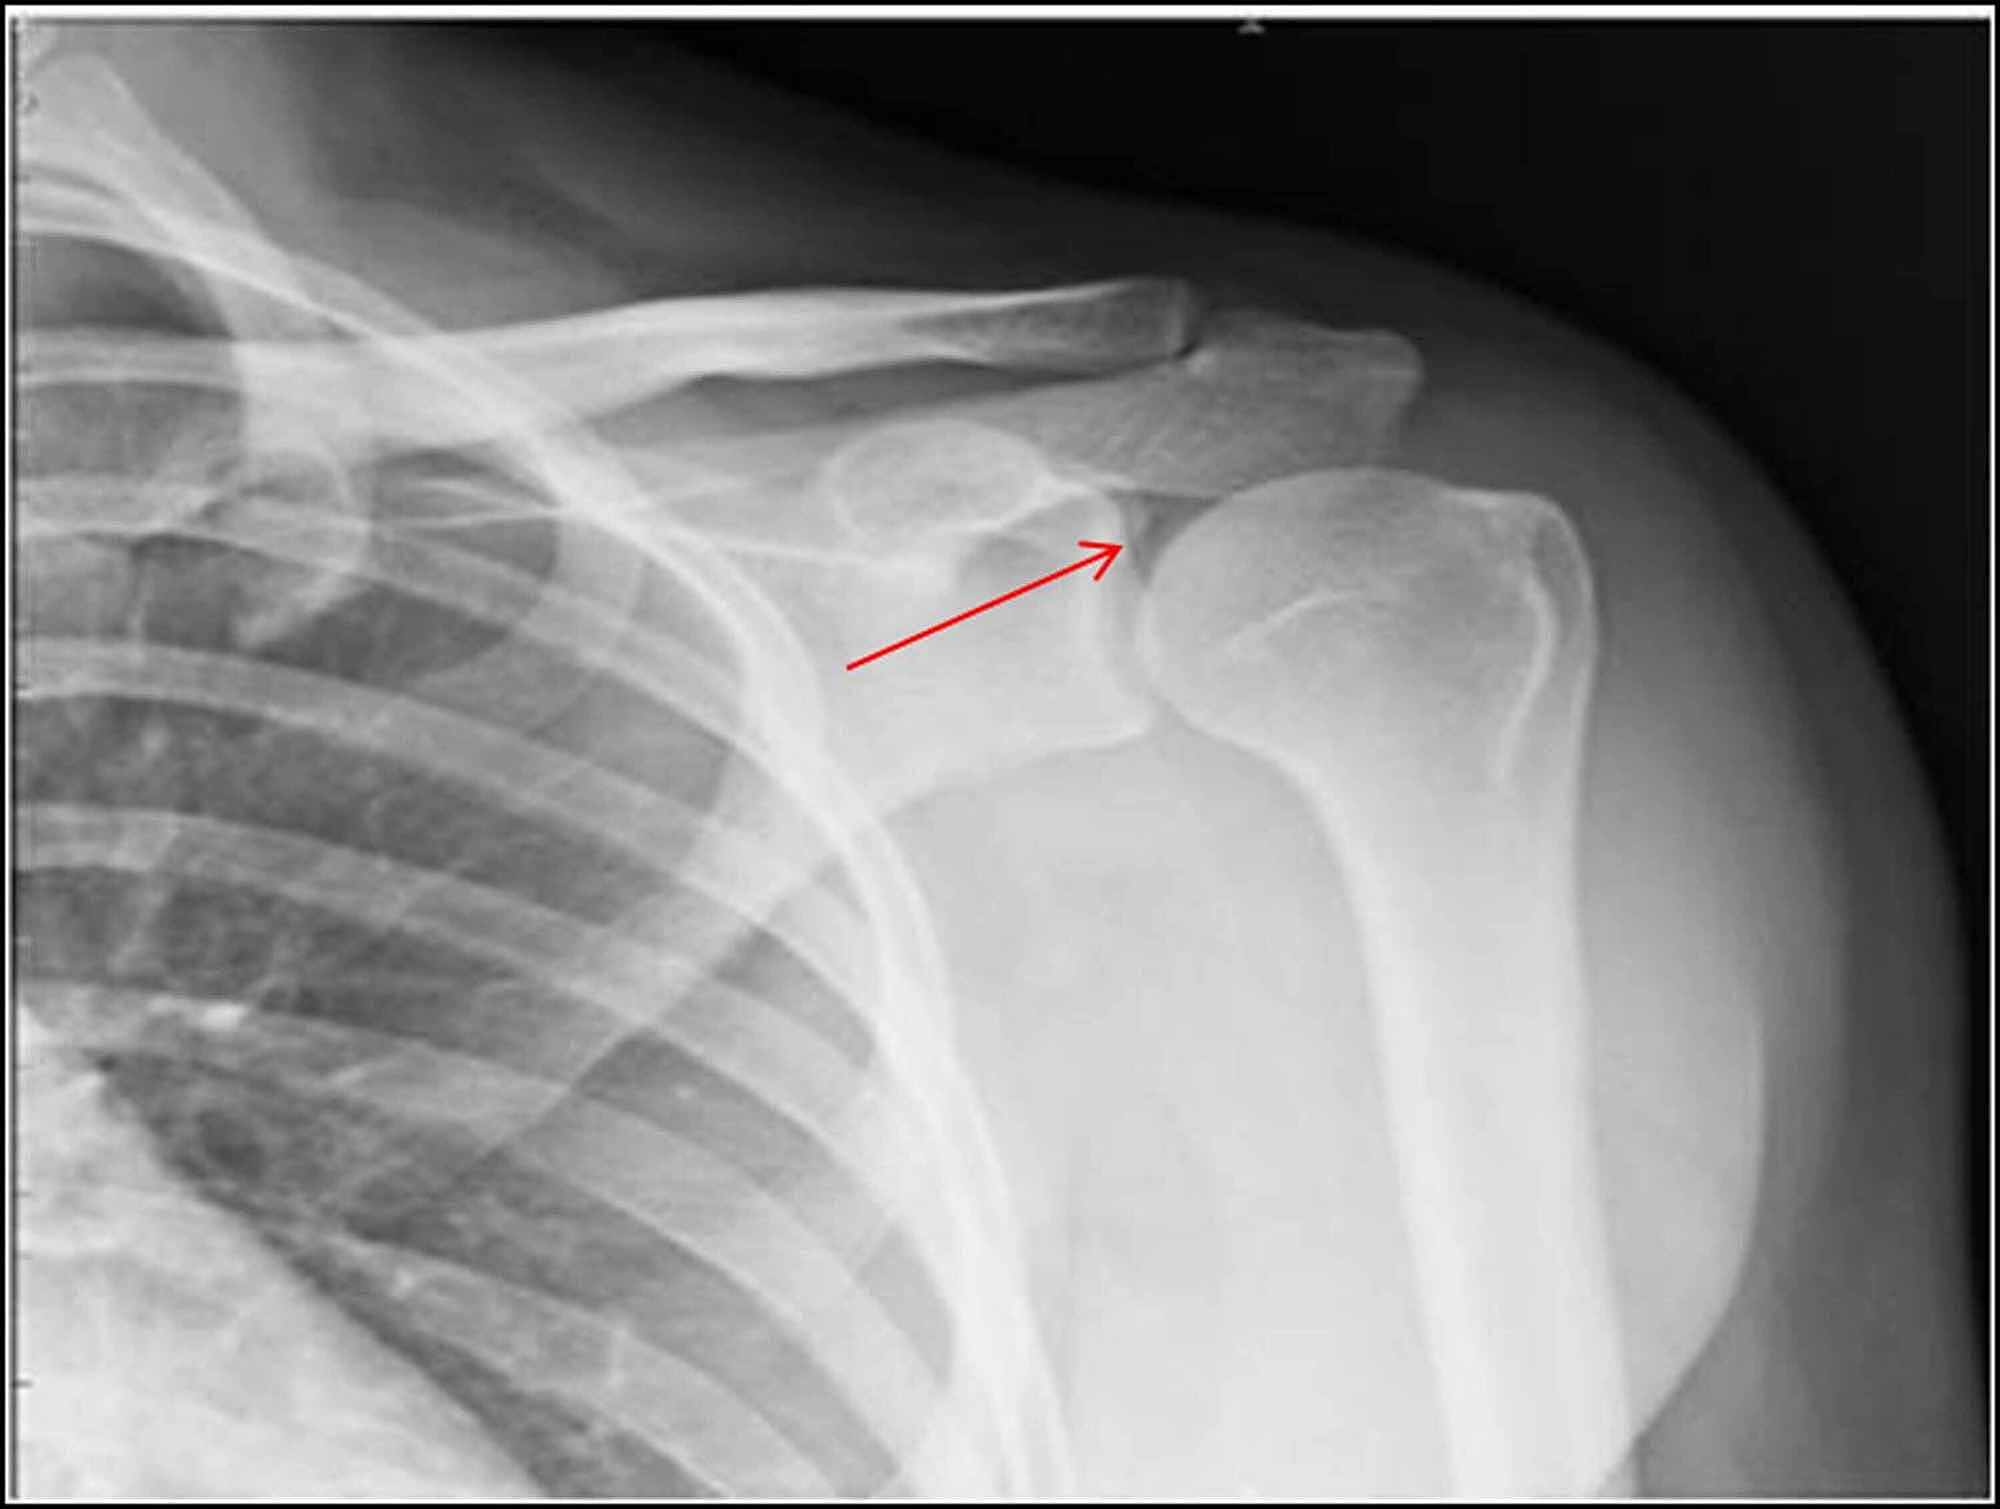

From www.cureus.com

Cureus The Air Inside Joint A Sign of Disease Pathology or a Benign How Does Air Get In Your Joints Back in april 2015, researchers from the university of alberta published a paper based on mri imaging of finger joints being cracked saying. Air bubbles forming in the joint spaces are the most common cause of popping noises. Some causes of crepitus may cause pain, while other causes, like air bubbles in a joint, may not. One of the best. How Does Air Get In Your Joints.